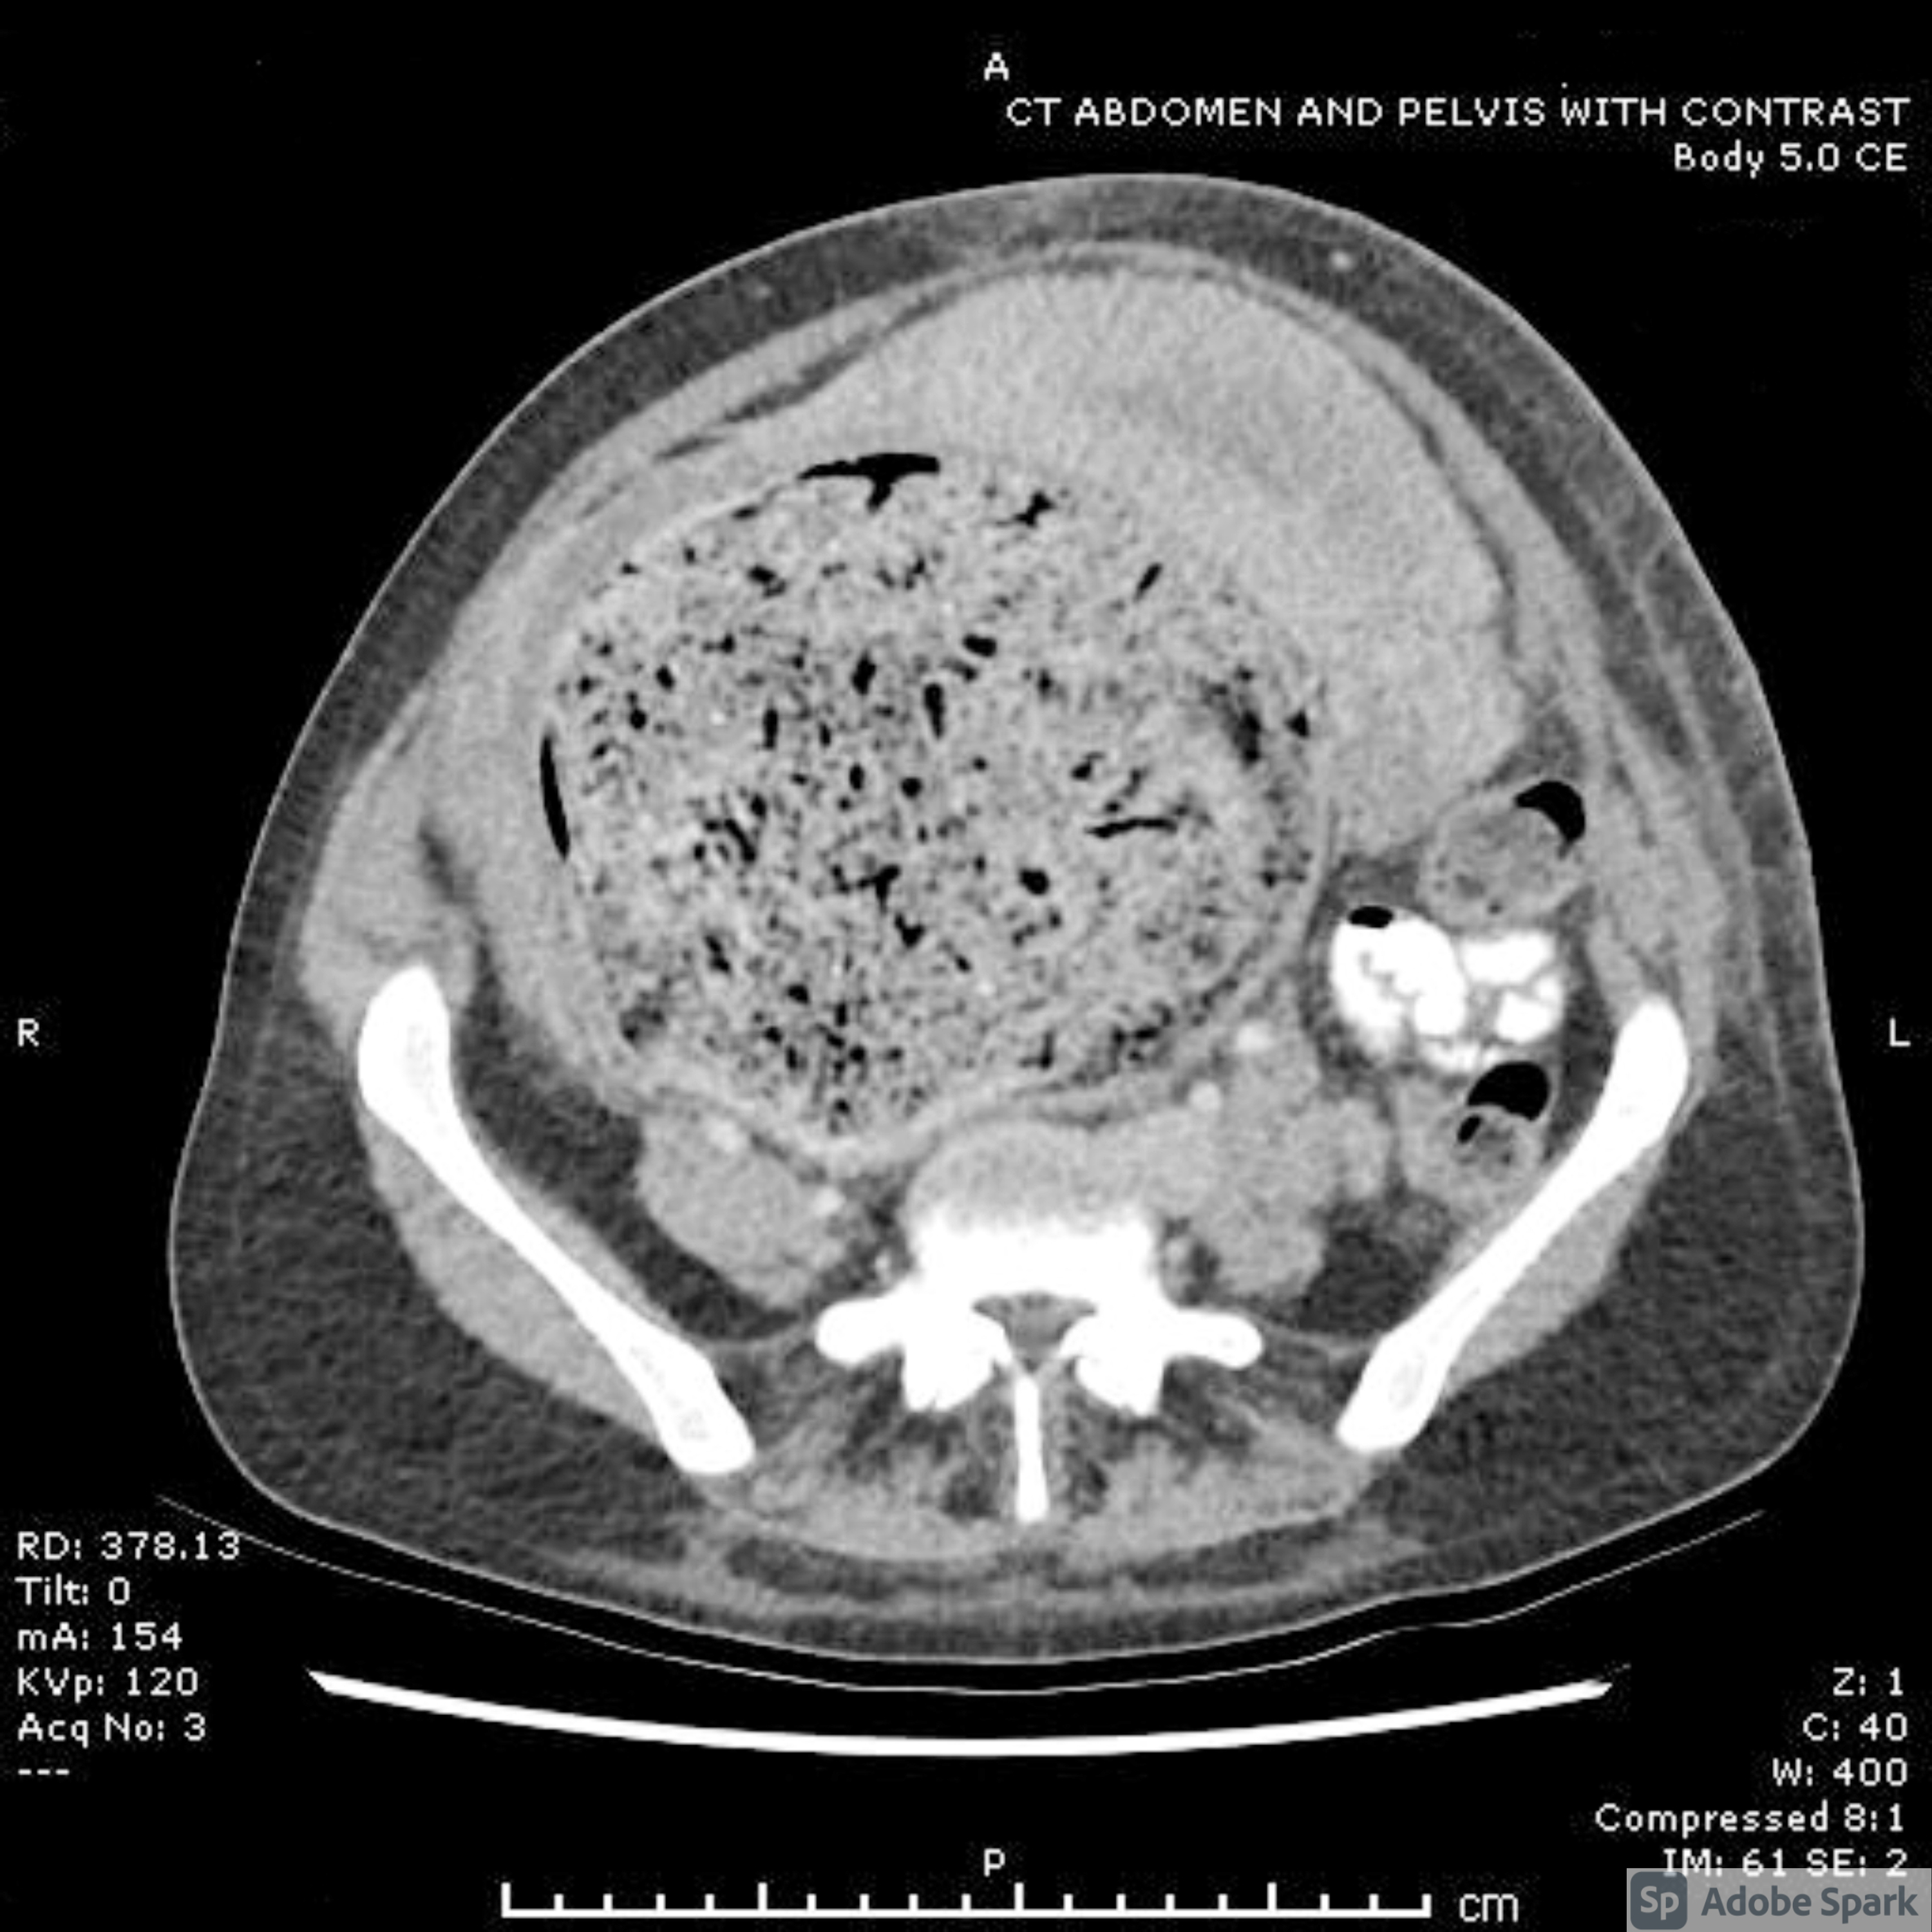

Cureus Acute Pulmonary Edema In Pregnancy Fluid Overload Or Atypical Pre Eclampsia